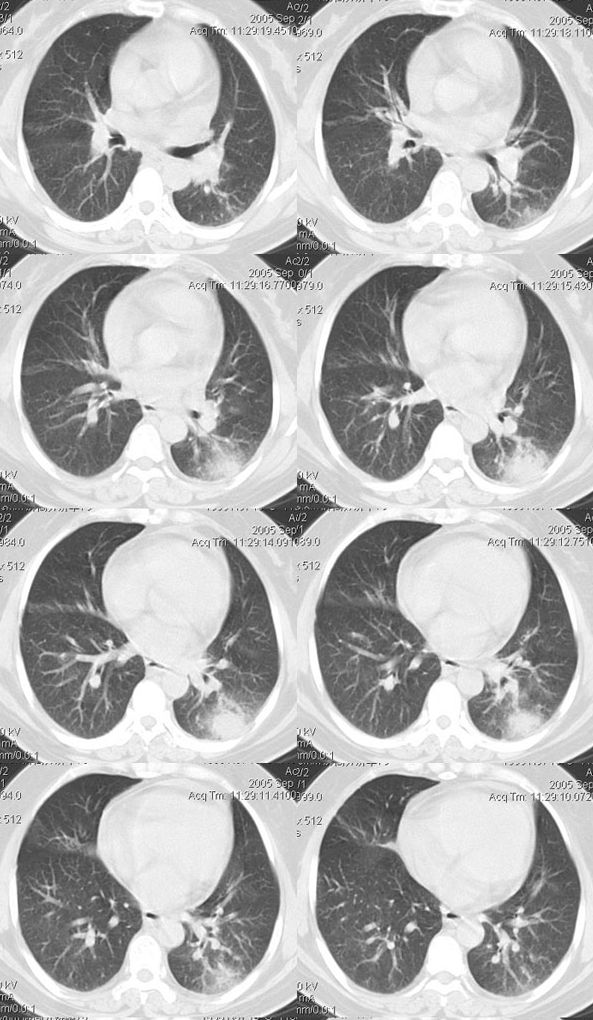

(1)发生部位:炎性假瘤可发生在两肺的任何部位,但多位于肺的表浅部位,邻近胸膜处或者靠近叶间裂。可以跨叶生长,原因可能是跨叶浸润的炎症使得假瘤跨叶融合的结果。

(2)假瘤形态:炎性假瘤的形态不一,可呈圆形.椭圆形或类圆形,也可呈驼峰状或不规则图形。

(3)假瘤大小:多数假瘤的直径在2-4cm,也可大于5cm,少数甚至大于10cm.

(4)假瘤密度:炎性假瘤一般为中等密度,密度均匀。而脓性炎症形成的假瘤则有时可见小空洞。空洞可以单发也可多发。少数瘤体切开时可见脓性物。

(5)假瘤边缘:

①有假无假性包膜者边缘清楚。有的由于肿块不规则可表现分叶状。

② 无假性包膜者,假瘤周围有纤维化和多种细胞成分侵润,表现为片状、边缘模糊的团块状影。或有轻度的渗出性病变,边缘模糊,以组织细胞围增生型多见。有的假瘤周围还可以出现类似周围型肺癌的放射冠状表现。

(6)邻近改变:位于肺周边部的假瘤,其邻近胸膜可见局限性粘连增厚。位于近肺门区的假瘤,偶可阻塞支气管,形成肺叶不张而将假瘤包裹,甚似中央性肺癌,但不出现肺门或纵膈淋巴结肿大。

(7)王学成等指出肺炎性假瘤胸腔无胸水出现,有利于与肺癌、肺结核鉴别。

(8)动态观察:假瘤可在数年之内无明显增大,当并发急性炎症时,可以使“瘤”体增大,少数炎症可以发生癌变。

(9)增强检查大多数肿块可见较显著的均匀强化,少数仅见肿块周围部强化甚或肿块不强化,这与肿块的组织结构成分,特别是血管成分有关。少数病人可见同侧肺门及纵隔淋巴结肿大,其直径常小于1.5cm.